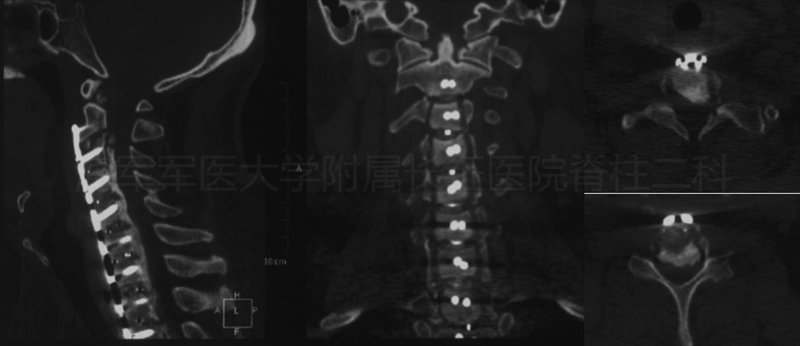

术后侧位平片矢状位MRI和矢状位、水平位CT

术后CT